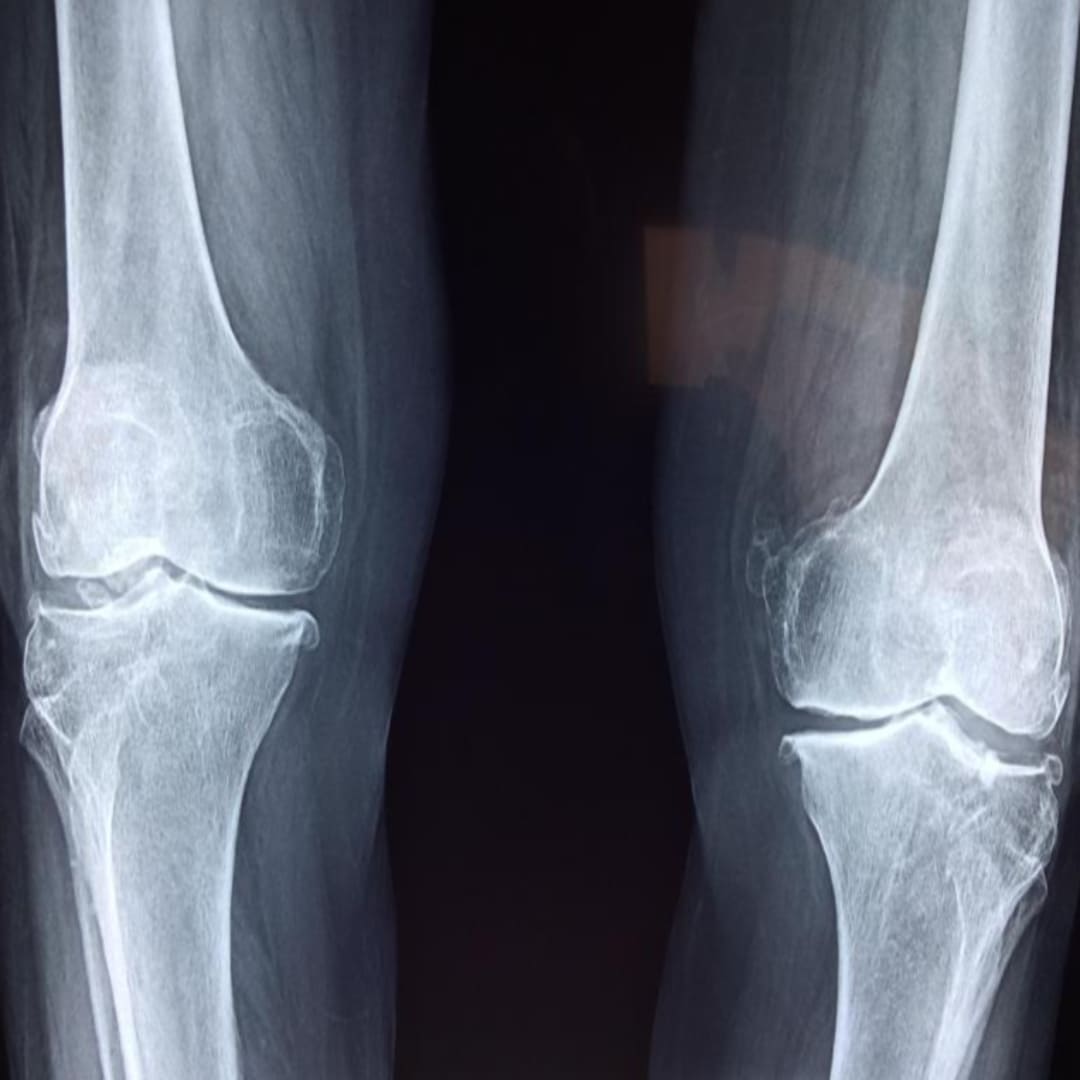

관절은 뼈와 뼈를 연결하는 중요한 부위로, 그 사이에는 마찰을 줄여주는 연골이 존재합니다. 그런데 나이가 들거나 과도한 사용, 혹은 잘못된 자세 등으로 인해 이 연골이 서서히 닳기 시작하면, 뼈와 뼈가 직접 맞닿아 염증과 통증을 유발하게 됩니다. 이것이 바로 퇴행성 관절염의 대표적인 증상입니다.